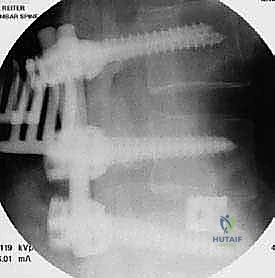

الخطوة 4: زراعة القفص والطعم العظمي (Cage Insertion)

يتم إدخال قفص مصنوع من مادة PEEK أو التيتانيوم، مملوء بطعم عظمي (يؤخذ غالباً من المريض نفسه أو طعم صناعي)، في المساحة الفارغة. هذا القفص يعيد الارتفاع الطبيعي للفقرات ويخفف الضغط عن منافذ الأعصاب.

تتم هذه الجراحات تحت التخدير العام، وتستغرق عادة من ساعتين إلى أربع ساعات حسب تعقيد الحالة. بفضل خبرة الأستاذ الدكتور محمد هطيف، يتم تنفيذ كل خطوة بدقة متناهية لضمان أعلى نسب النجاح.

يتم وضع المريض على بطنه. يتم عمل شق جراحي دقيق في أسفل الظهر. باستخدام أجهزة الملاحة الجراحية والأشعة السينية الحية (Fluoroscopy)، يتم تحديد المستويات الفقرية المستهدفة بدقة.